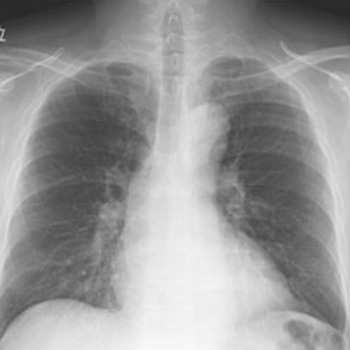

一般撮影

フラットパネルシステムが導入され、画質が向上し、被ばく線量の低減(従来の約40%カット)も図ることができました!